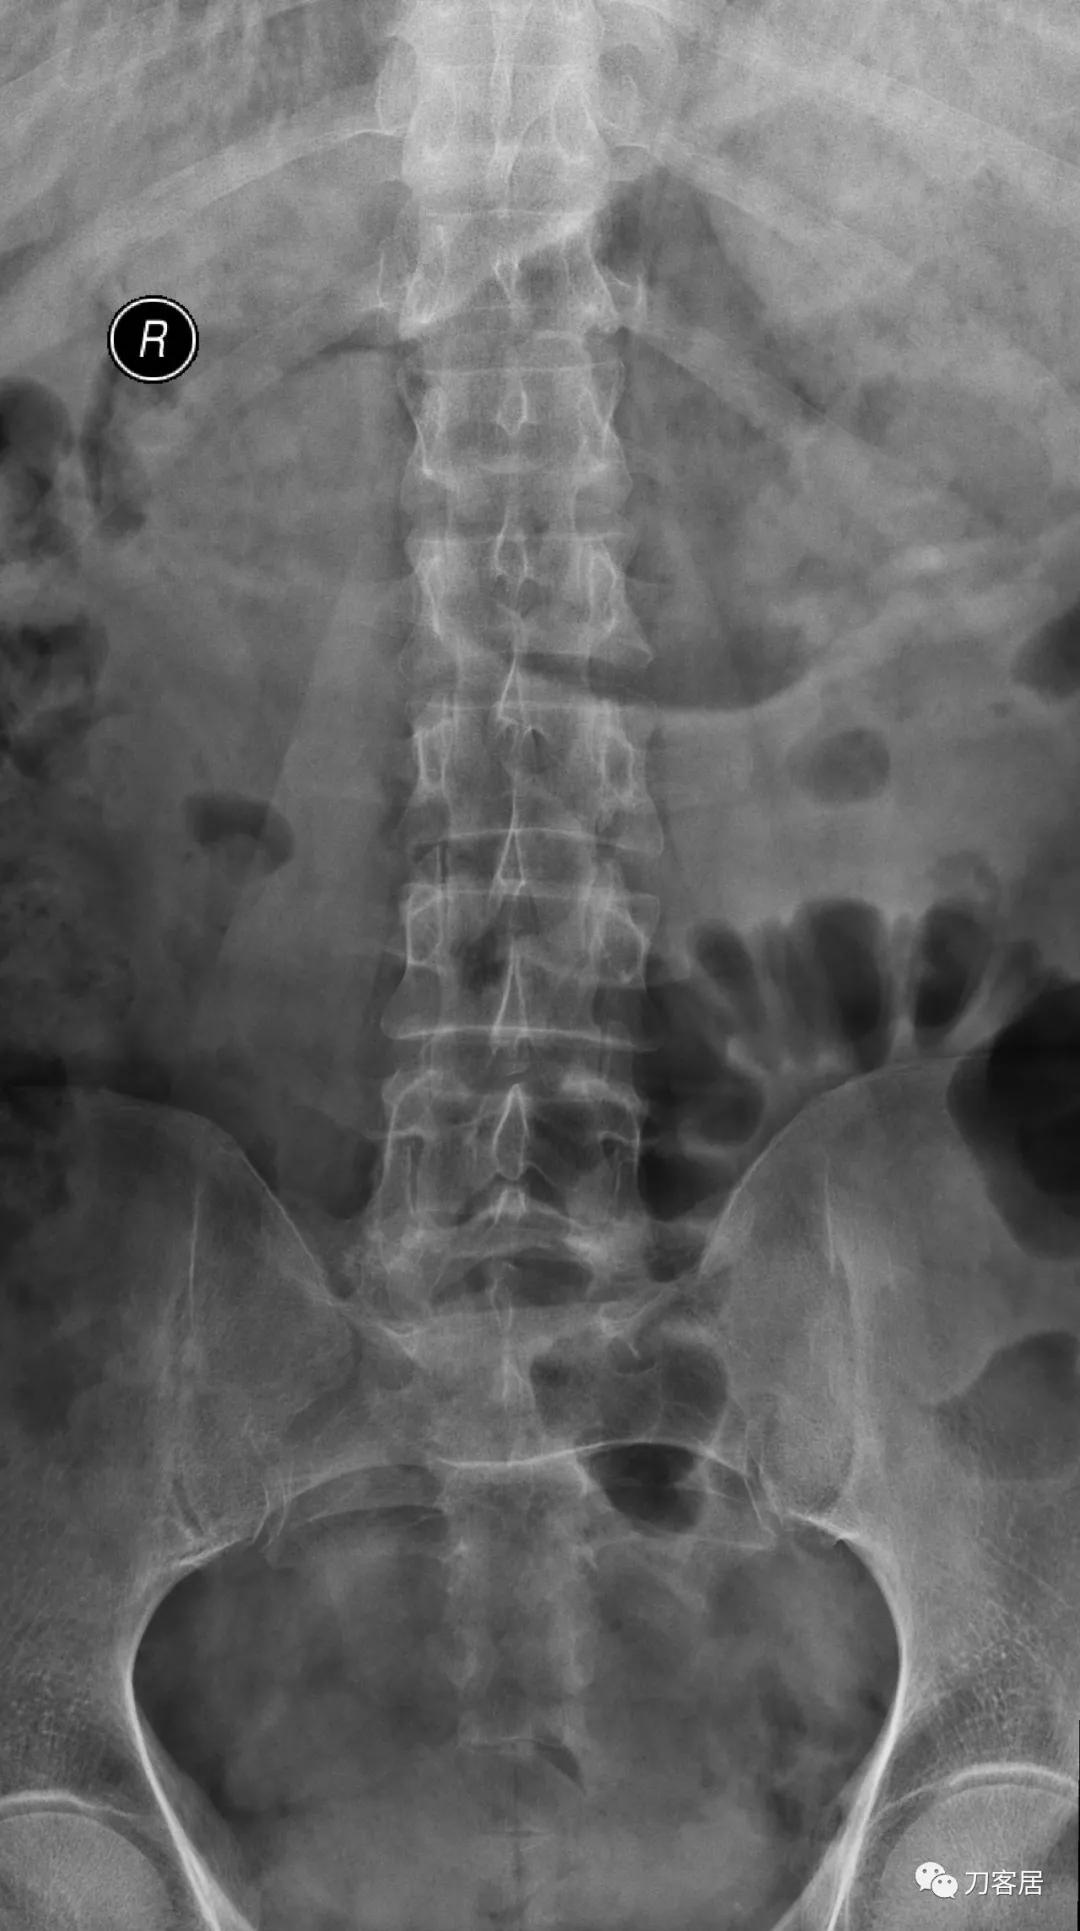

自带影像学检查提示腰5椎体前滑脱,腰5峡部裂,椎管狭窄不严重。

诊断:腰5峡部裂,腰5椎体前滑脱1度,骨质疏松症。

图3. 20210616术前腰椎正位X线片